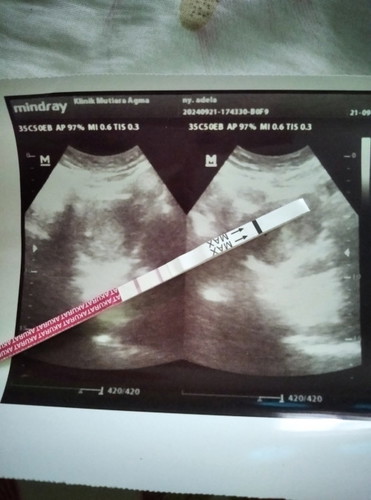

Kmrn USG msh 4mingguan Bun msh nampak kantung ny aja. Tp udah mulai mual2. Normal GK sih?

normal bun, biasanya janin terbentuk di usia 8-12w, jd dibawah itu biasanya msh berupa kantong.